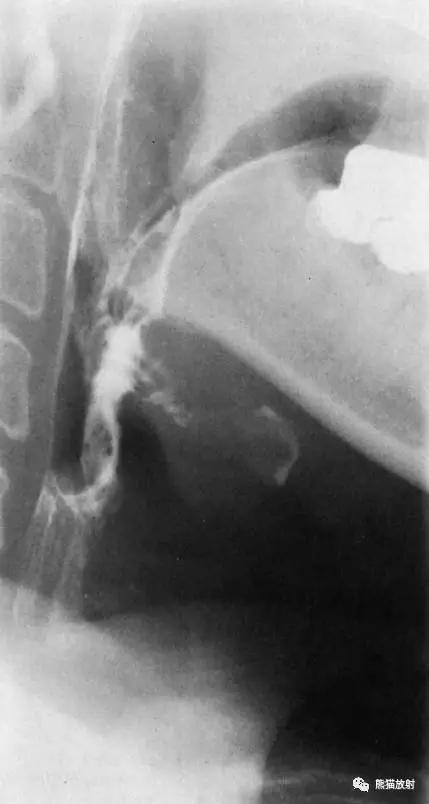

2 Lateral View of the Hypopharynx 下咽部( 侧位 )

1 Uvula 悬雍垂,2 Cervical spine (axis) 颈椎,3 Tongue 舌,4 Oropharynx 口咽,5 Mandible 下颌骨,6 Vallecula 会厌谷,7 Larynx 喉咽,8 Hyoid bone 舌骨,9 Piriform recess 梨状隐窝,10 Ventricle of the larynx 喉室,11 Esophagus 食管,12 Trachea 气管